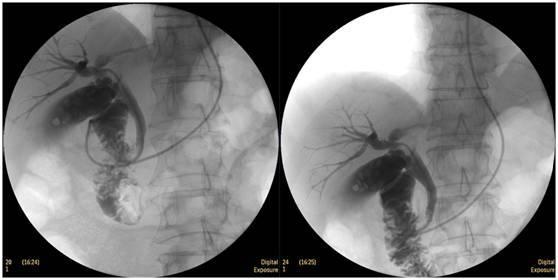

膽囊結(jié)石

ERCP膽囊顯影,見多枚結(jié)石影。

鼻膽管造影

立位注入造影劑,膽總管顯影好,稍擴張,未見結(jié)石影。

膽總管結(jié)石

柱狀球囊擴張完全,膽總管擴張,下段見充盈缺損影。

膽總管擴張,下段見明顯充盈缺損(上圖為反片且局部放大后效果)

柱狀球囊擴張膽總管下段及乳頭(上圖為使用取石網(wǎng)籃取石)。